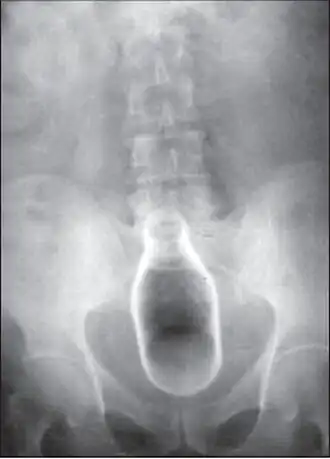

Стеклянная бутылка в просвете прямой кишки на рентгенограмме | |

Обычно делают несколько рентгеновских снимков, чтобы точно определить место нахождения инородного тела. Инородные тела из малоконтрастного материала (например, пластика) могут потребовать ультразвукового исследования или компьютерной томографии.[28] Магнитно-резонансная томография противопоказана, особенно если неизвестен материал инородного тела. Инородные тела прямой кишки могут проникать глубоко в толстую кишку, при определённых обстоятельствах вплоть до правого изгиба ободочной кишки.[9]